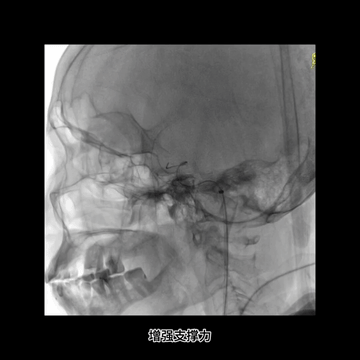

微导管造影证实真腔,再次送入和释放支架。

抽拉结合取栓后造影示:闭塞完全再通,取出数块大血栓。

术后第2日CT平扫:右侧半球仅见少许片状低密度梗死灶。

取栓后患者快速恢复,术后第2日NIHSS将至2。